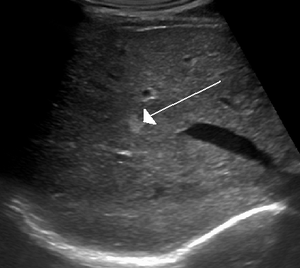

Liver cavernous hemangioma

Cavernous hemangiomas are the most common benign tumors of the liver.[4] Usually one tumor exists, but multiple lesions can occur in the left or right lobe of the liver in 40% of patients.[5] Their sizes can range from a few millimeters to 20 centimetres. Those over 5 cm are often referred to as giant hemangiomas.[5]

Usually the first step a doctor uses is an X-ray computed tomography (CT) scan to identify cavernous hemangioma. Magnetic resonance imaging (MRI) can be used to identify cavernous hemangioma. The phrase “bag of worms” is usually used to describe the appearance of hemangiomas in such images.[15] Angiography can be used by using a dye that is injected into the blood stream allowing for the contrast of hemangioma to show up. Additionally, doctors can use a biopsy by obtaining a sample of tissue of the tumor using a needle to examine it under a microscope. It is essential to diagnose cavernous hemangioma because treatments for this benign tumor are less aggressive than that of cancerous tumors, such as angiosarcoma. In some cases, it is possible for a surgery to be used as a method of diagnosis if imaging is not enough. The lesion is viewed under the microscope to diagnose cavernoma.[16]